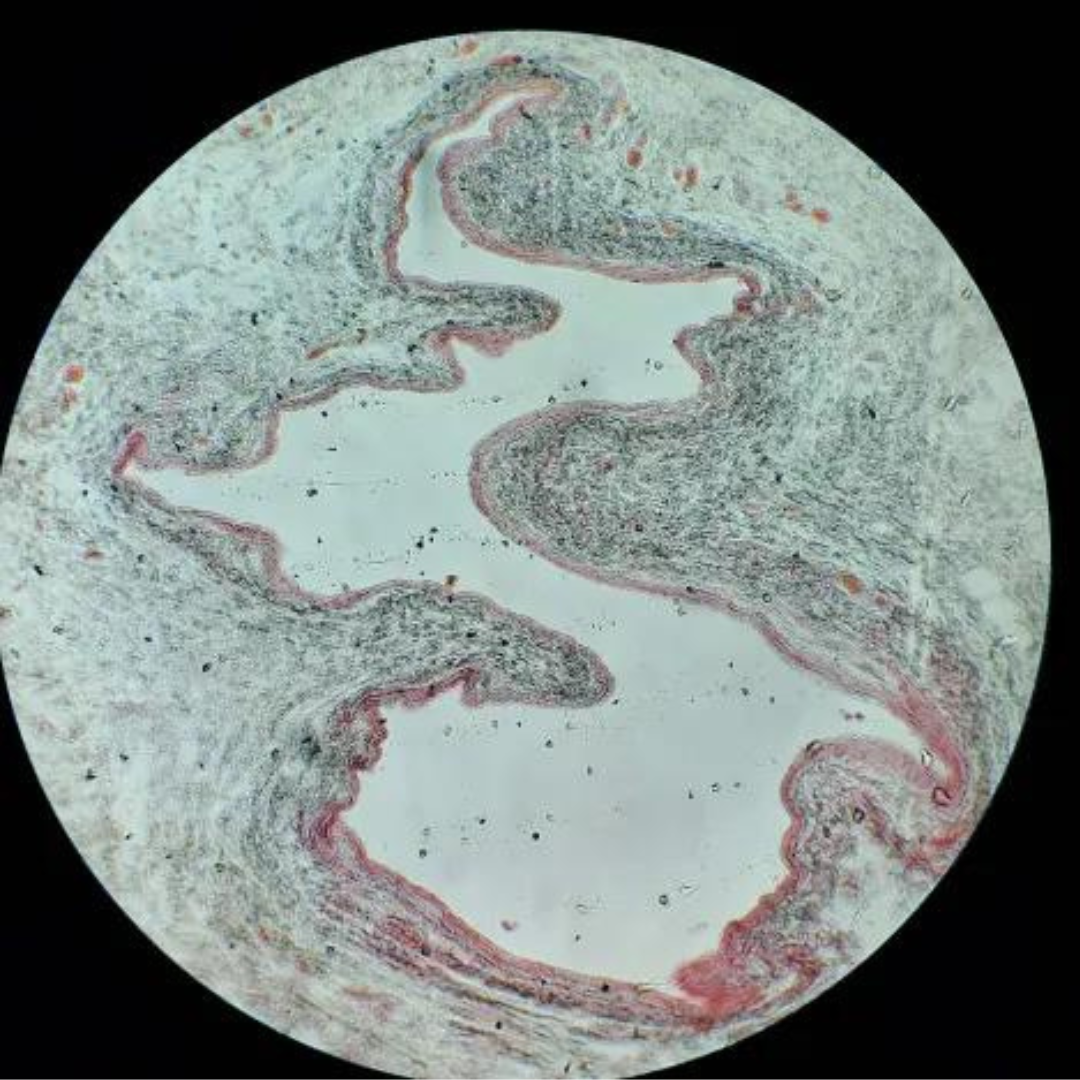

Large Veins

Large Veins

Large Veins

Large Veins